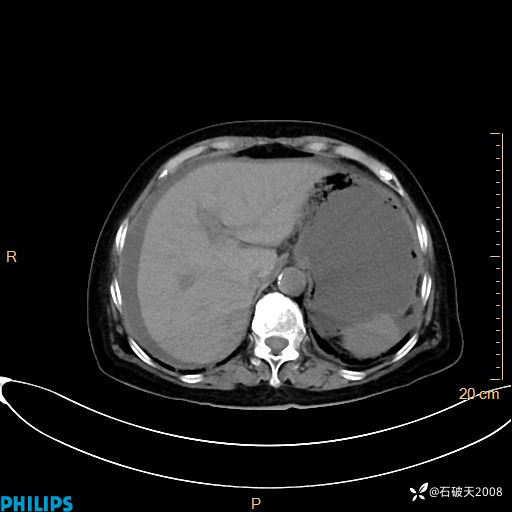

平扫